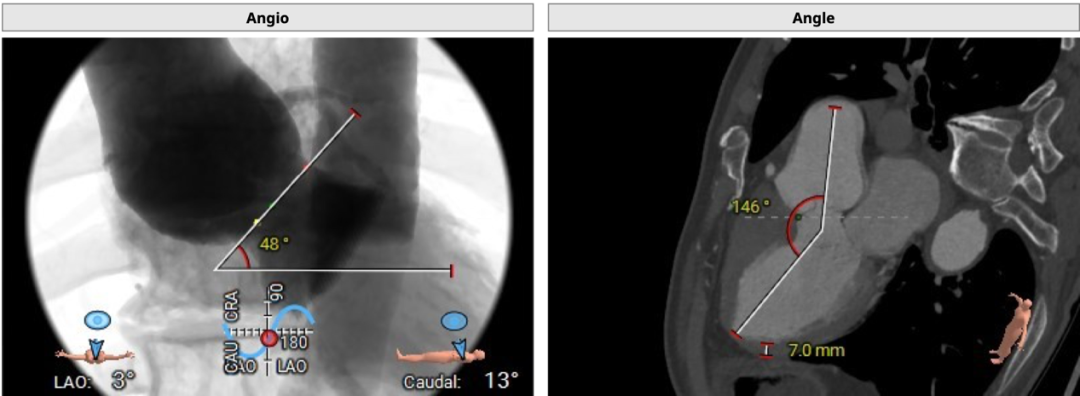

术中建议造影角度LAO 3°,CAU 13°:

心室角度48°,入路角度146°: